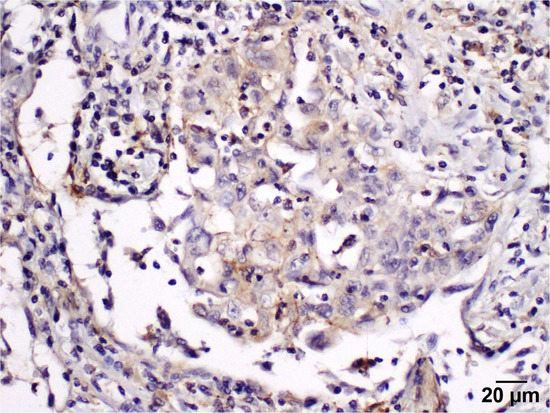

2.4. Immunohistochemistry

2.5. To Evaluate the Level of PD-L1 Expression in the Stroma, the Percentage of Positively